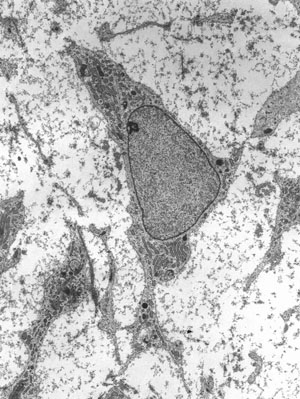

Искусный гистолог, Максимов впервые проследил все ключевые этапы гематопоэза — сложного и разветвленного процесса образования крови, обнаружив, что самые разные кровяные клетки образуются из одинаковых предшественников, похожих на лимфоциты. Такие клетки он назвал стволовыми (Stammzellen). Ученый еще не вкладывал в этот термин современного смысла, используя его скорее как описательный. Тем не менее с его руки редкое словечко вошло в научный обиход. Полвека спустя, когда американцы Тилл и Маккалох провели свои легендарные эксперименты по восстановлению нарушенного радиацией кроветворения у мышей пересадкой им одной-единственной зародышевой клетки, название для нее казалось уже совершенно естественным: стволовая.